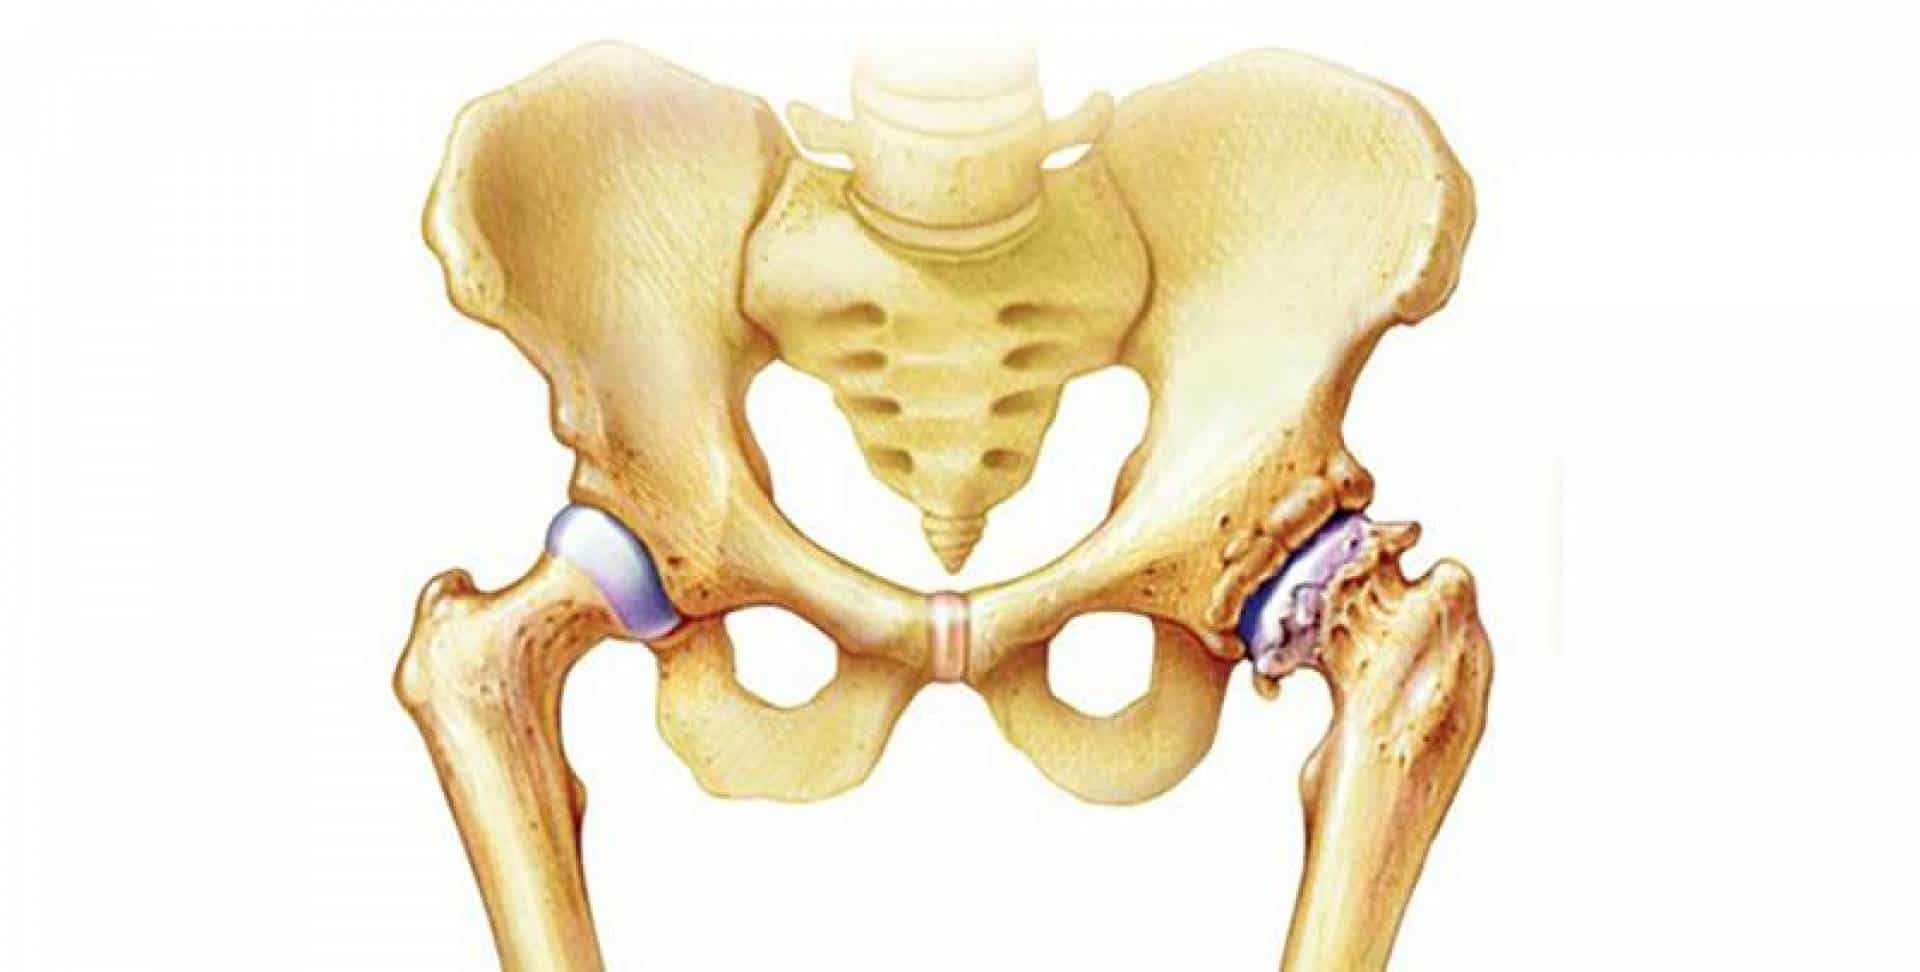

Болезнь чаще поражает крупные суставы. К специалистам обращаются пациенты, у которых диагностируется остеоартроз коленного сустава, который нередко формируется в результате бытовых и профессиональных травм. У пожилых людей на фоне остеопороза, нарушений обмена веществ и генетической предрасположенности может развиваться остеоартроз тазобедренного сустава, приводящий к инвалидизации и значительным двигательным ограничениям в будущем. Люди пенсионного возраста в группе риска по развитию опорно-двигательных нарушений. После 60 лет у большинства из них развивается остеопороз и остеоартроз кистей рук и других крупных суставов.

У 674 пациентов (43 %) отмечено сочетание коксартроза с остеохондрозом. Двухстороннее поражение тазобедренных суставов наблюдалось в 29% случаев.

Для своевременного выявления ранних проявлений коксартроза нами применяется комплексный подход в диагностике данной патологии, включающий: опрос, осмотр сустава, проверка объема движения в нем, рентгенографию, компьютерную томографию (КТ), магнитно-резонансную томографию (МРТ) и ультразвуковое исследование (УЗИ) тазобедренного сустава.

У 56 (32,5%) пациентов отмечены периодические ноющие боли в области тазобедренного сустава, реже в области бедра или коленного сустава, иногда после сна, небольшое ограничение движений, появление хромоты, особенно после длительной ходьбы и стояния на ногах. Амплитуда движения в суставе не ограничена, мышечная сила не изменена.

На рентгенограммах тазобедренный сустав сохраняет нормальную форму, суставная щель умеренно или неравномерно сужена с субхондральным склерозированием костных суставных поверхностей, непостоянными краевыми костными разрастаниями (I стадия).

У 116 (67.5%) пациентов имелись постоянные боли, иррадиирующие в бедро, паховую область, хромота, значительное ограничение движений, ограничение внутренней ротации и отведения, непостоянный хруст в суставе при движении.

Рентгенологически суставная щель может быть равномерно или неравномерно сужена, ацетабулярная суставная впадина уплощена, присутствуют явления субхондрального склероза, краевые костные разрастания. Конфигурация головки бедренной кости, как правило, не нарушена (II стадия).

В подавляющем большинстве случаев диагноз коксартроза ставится при рентгенографии, где видны изменения формы и структуры костей, составляющих тазобедренный сустав. Однако рентгенографически в ряде случаев затруднительно зафиксировать ранние проявления артроза, так как хрящевая ткань суставных поверхностей на рентгеновских снимках не отображается и мы можем судить о дегенеративном процессе, когда он достаточно выражен, вызывая изменения ширины просвета рентгеновской суставной щели.

Применение диагностического ультразвука позволяет получить информацию о наличии минимального количества выпота в тазобедренном суставе, синовита и сопутствующего им бурсита, что было выявлено в 34 % случаев, в выявлении которых УЗИ по информативности не уступает МРТ. При УЗИ в 80% отмечалось уменьшение толщины гиалинового хряща.

КТ тазобедренного сустава проведено с 2002 года в 80, МРТ с 2011 года — в 22 случаях. Предпочтение следует отдать МРТ, так как при данном виде исследования можно четко визуализировать суставную капсулу и связки, идентифицировать даже поверхностные изменения хрящевого слоя, а также мелкие очаги субкортикального трабекулярного отека губчатого вещества костной ткани. КТ позволяет оценить минимальные изменения структуры и формы костной ткани, однако в общем объеме получаемой информации уступая МРТ в информативности. При углубленном обследовании для уточнения диагноза «коксартроз» и степени его выраженности можно рекомендовать проведение именно МРТ тазобедренных суставов.